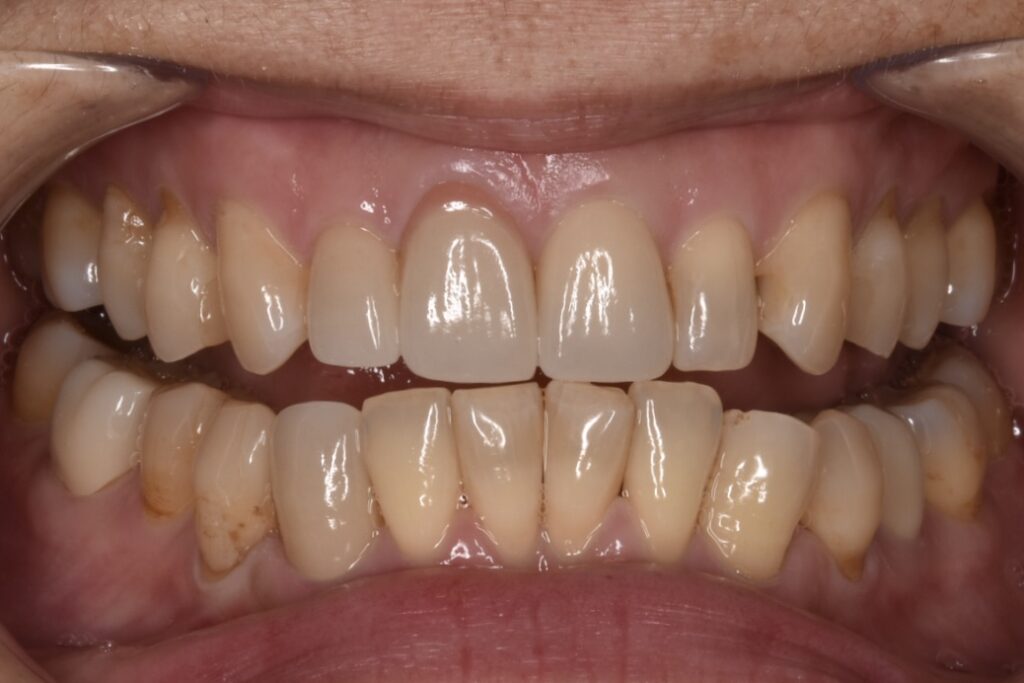

モニター様①

こちらのお客様は全ての銀歯と古い被せ物をやりかえしてくださったモニター様です。上の前歯と下の歯の犬歯がよくわかります。見える部分の銀歯も無くなりました。*ダイヤモンド匠プラン